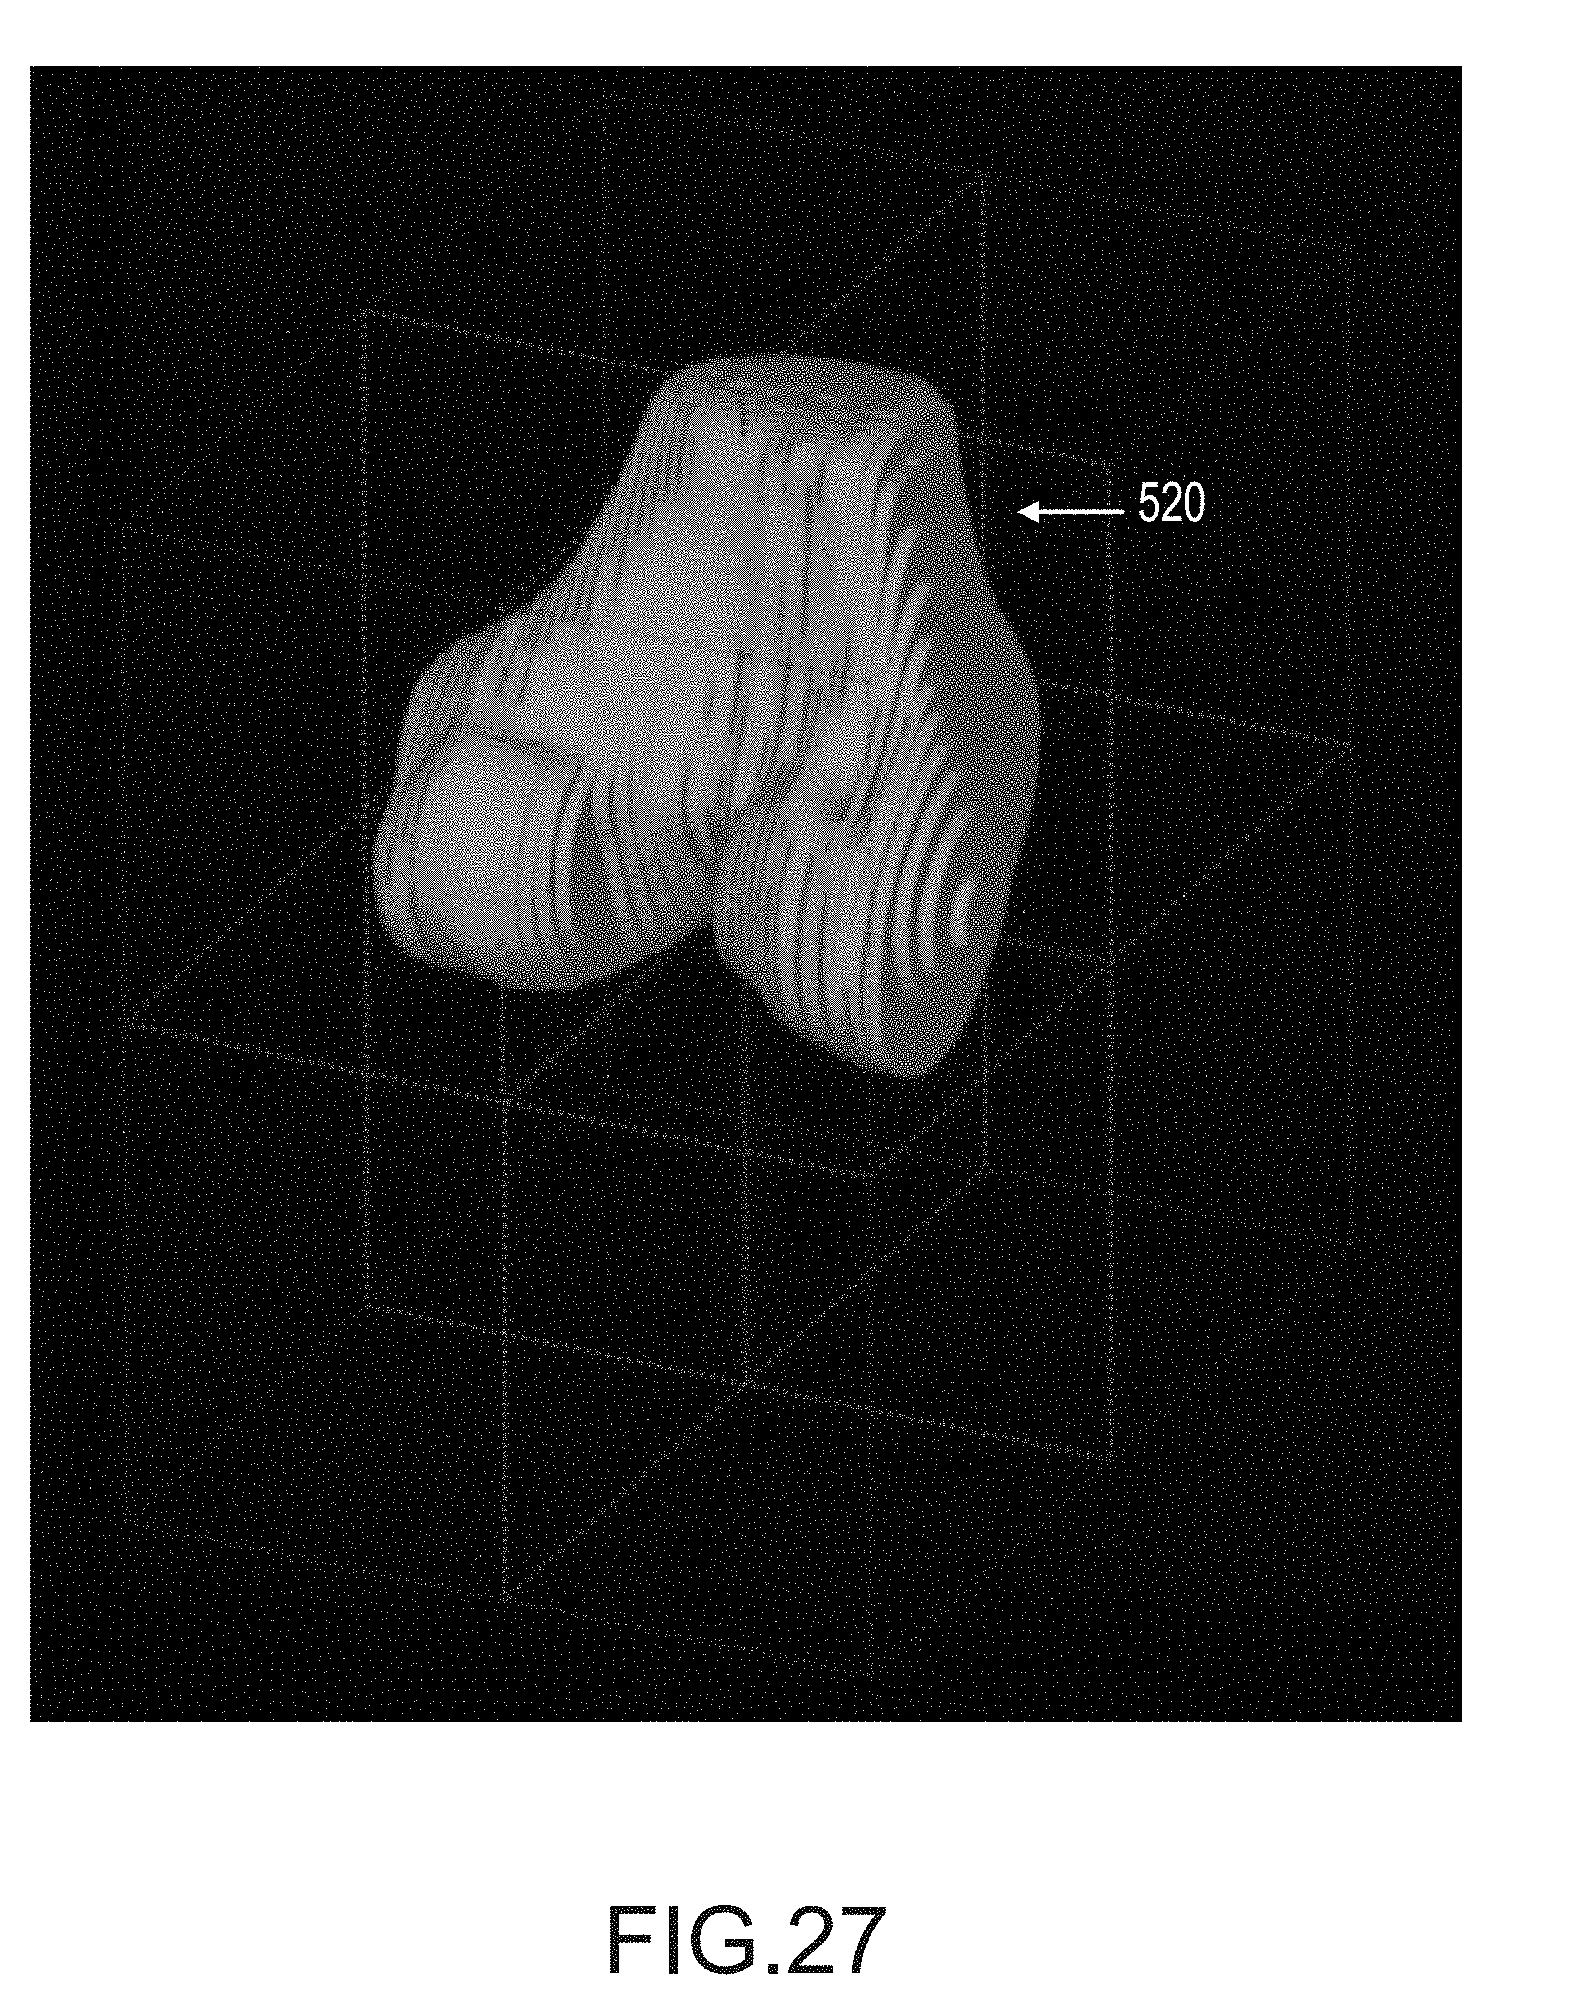

FIG. 27 depicts a 3D slice visualization of a femur showing the voxels inside of the spline curves.

Once the technician is satisfied with all of the femur spline curves in the scan slices, operation 256 generates a watertight triangular mesh geometry from the femur segmentation that approximates the 3D surface of the femur. The mesh closely follows the femur spline curves 270 and smoothly interpolates between them to generate a 3D surface model of the femur. FIG. 9 depicts typical 3D mesh geometry 290 of a target femur generated by one embodiment. Such a 3D model may be a 3D surface model or 3D volume model resulting from open-loop contour lines or closed loop contour lines, respectively. In one embodiment, such a 3D model as depicted in FIG. 9 may be a bone model 22 or an arthritic model 36.